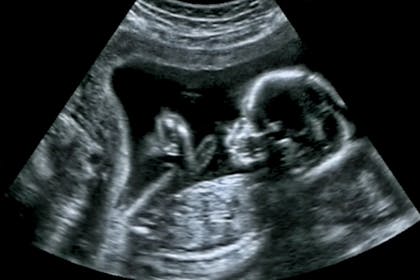

Week 18 Ultrasound What It Would Look Like

Family Friday Vol 11 Baby Gender Girl Ultrasound Pictures Ultrasound Gender Ultrasound Gender Prediction Gender Reveal Ultrasound Packages - Starting at 69. The genetic test is designed to work in conjunction with an ultrasound scan. In fact according to the research the accuracy of the 11-week.

Early Ultrasound Gender Prediction Store Submit Your Scan. According to Ultrasound in Medicine and Biology Between 6-9 weeks gestation 972 of male fetuses have a placenta location on the right side of the uterus whereas 975. F inding the gender of your baby at 11 weeks of pregnancy scan may not yield perfectly accurate results.

14 Week Ultrasound Guesses In Ultrasound Gender Prediction Forum